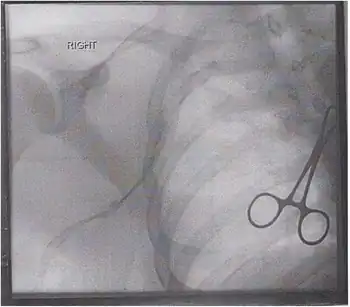

Paget–Schroetter disease (also known as venous thoracic outlet syndrome), is a form of upper extremity deep vein thrombosis (DVT), a medical condition in which blood clots form in the deep veins of the arms. These DVTs typically occur in the axillary and/or subclavian veins.[1]

The traditional treatment for thrombosis is the same as for a lower extremity DVT, and involves systemic anticoagulation to prevent a pulmonary embolus.[10] Some have also recommended thrombolysis with catheter directed alteplase or mechanical thrombectomy with a large bore catheter and manual aspiration providing definitive intervention with an endovascular approach.[11] If there is thoracic outlet syndrome or other anatomical cause then surgery can be considered to correct the underlying defect.[12]